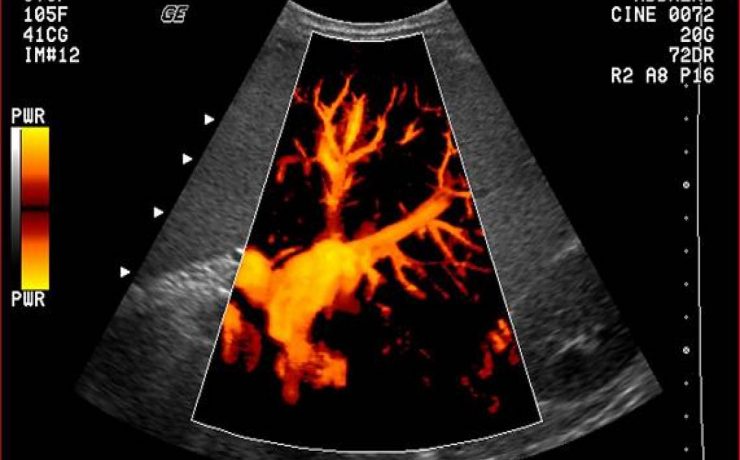

El diagnóstico de tumores ováricos durante el embarazo es cada vez más frecuente como consecuencia del mayor uso rutinario del ultrasonido desde etapas tempranas de la gestación. Si bien la frecuencia sigue siendo baja en relación con otras neoplasias asociadas al embarazo, se reporta una incidencia menor de 5%. Casi